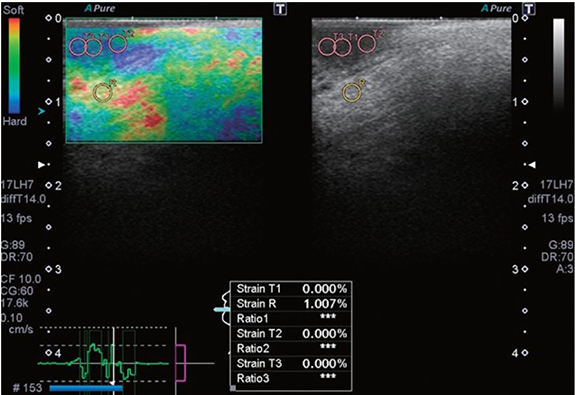

Tissue stiffness increases as cancer progresses, including at the early stages. Recent studies have evaluated the use of ultrasound elastography for estimating the stiffness of oral lesions. Strain elastography is based on imaging tissue strain in response to an external compressive force [140]. Softer tissues respond with higher strains than stiffer tissues. Strains are measured by analyzing displacements of ultrasound RF echoes from tissues in real-time. A ratio of the strains of the tumor and surrounding healthy tissue is used to gauge relative differences in stiffness. Aktar et al were the first to investigate strain elastography for SCC of the tongue of patient volunteers [140]. They found that normal tongues had higher strain ratios than those with SCC. Later studies explored the diagnostic feasibility of intraoral strain elastography for early-stage tongue carcinoma (figure 5) and reported clear discrimination between non-malignant lesions and carcinoma [141, 142]. Strain elastography is simple to implement and provides relative stiffness images in a manner analogous to palpation. However, strain images are confounded by artifacts caused by geometry effects, tissue nonlinearity due to excessive strain, and non-uniform stress distribution in tissues [143].

Figure 5. A strain elastogram (left) and B-mode image (right) of tongue squamous cell carcinoma in a 59 year-old man. The average strain of the normal tissue (R) is higher than that of the carcinoma (T1-3). Reprinted from [142], Copyright (2018), with permission from the Korean Academy of Oral and Maxillofacial Radiology.

Standard image High-resolution imageUltrasound shear wave elastography has recently been investigated for oral cancer diagnosis. This technique involves applying an external mechanical source to generate propagating shear waves in tissue. Tissue is detected by ultrasound imaging, and the measured speed of the shear wave is used to estimate tissue elasticity [143]. Thus far, only one study by Ogura et al has reported using shear wave elastography for tumor evaluation in the oral cavity [144]. They found that the stiffness of the tumors was more than ten times those of benign lesions. However, delineating tumor boundaries in the elasticity images was challenging, and thus, their results may have been confounded by boundary artifacts. Therefore, more studies are necessary to elucidate the role of shear wave elastography on oral cancer staging.